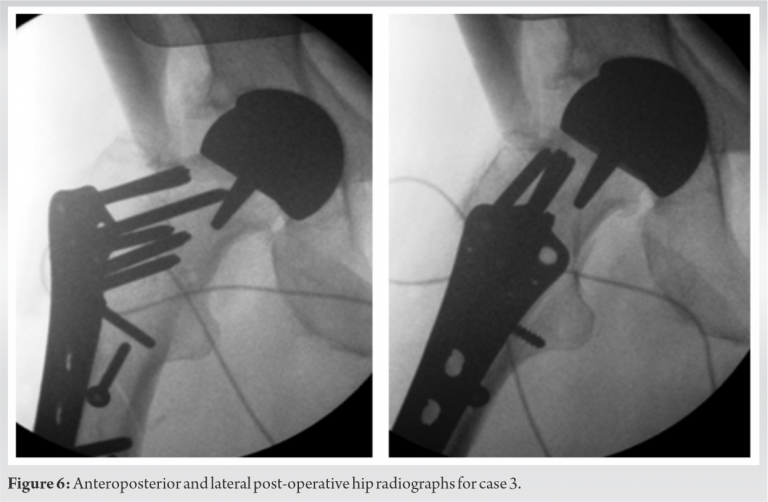

The three cases that we describe in this paper are homogenous in presentation, treatment and outcome, and therefore presented in the table below (Table 2). Pre-operative (Fig. 1-3) and post-operative (Fig. 4-6) radiographs are also included for each of the cases. 3-D reconstructed images from a computerized tomography (CT) scan for case 3 can be visualized as part of (Fig. 3).

All patients were independently mobile, active with well-fixed and well-functioning RHAs before the date of injury. All patients suffered low-energy trauma causing the fracture. All patients underwent CT scans to further delineate the fracture pattern, to assess for radiographic signs of loosening, and to assess bone stock and suitability for fixation. Intraoperatively, patients were placed on a traction table. Optimal closed reduction of the fracture was achieved using intraoperative image intensifier (II). An extended direct lateral approach to the proximal femur was used. The fascia lata was divided along its fibers and the vastus lateralis split. Fracture reduction was improved, held with 2 mm Kirschner wires placed across the fracture site, and position confirmed with II. An anatomically contoured distal femoral variable angle LCP (VA-LCP) intended for the contralateral distal femur was measured, selected, and positioned in an inverted manner (proximal and distal ends reversed). The position was checked using image intensifier. A non-locking fully threaded cortical screw was inserted distal to the fracture site to seat the plate to bone. The senior author believes that it is essential to achieve the best possible screw hold in the neck, and therefore accept to some extent that the plate distally may not sit perfectly centered over the shaft of the femur. Shaft screws can be inserted distally through a minimally invasive plate osteosynthesis technique if desired. All patients were asked to partially bear weight on the operated side for 8 weeks. The time to radiographic union and the time to discharge from physiotherapy with achievement of previous level of function were recorded for two patients. One patient, case 3 (Fig. 3, 6), was lost to follow-up as she moved out of the country.

The literature suggests two distinct fracture modalities emerging in the presence of an RHA: “Atraumatic” and “traumatic.” The predominant mode is an insidious “atraumatic” type of injury that is more often intracapsular and frequently undisplaced or minimally displaced at presentation. According to Carrothers et al., this was the most common cause of revision in a review of 5000 resurfacings [4]. Although there have been reported cases of implant retention in these types of injuries [8, 9], revision arthroplasty is the recommended definitive treatment [2]. The “traumatic” modality occurs in the setting of trauma and therefore does not have a defined timescale or incidence. This subset of fractures is predominantly extracapsular in nature [15, 20], although sub-capital fractures can occur [18]. Favorable results have been reported for extramedullary fixation of intracapsular fractures within this “traumatic” group [34], although once again the recommended course of action is revision arthroplasty. Complex arthroplasty treatment decisions are best made in conjunction with multidisciplinary team (MDT) discussions, as these cases were [35]. This paper presents 3 cases of fracture around well-fixed and well-functioning hip resurfacing arthroplasties in independent high functioning individuals. To reduce the risks associated with revision arthroplasty and following discussions with the MDT as well as the patients, fixation was the selected treatment in these cases. A distal femoral VA-LCP condylar plate was used as it has more screw options compared to most proximal femoral locking plates. The reversed distal femur plate of the contralateral limb has an anatomic profile that sits well in the proximal femur and allows for increased screw purchase and screw density in the proximal femur around a RHA. It was also decided to avoid using plates with greater trochanteric extensions to reduce the risk of lateral hip pain, iliotibial band irritation, and need for future removal of metalwork. Patients are suitable for this treatment if they have a well-function and well-fixed prosthesis, if they have good bone stock and are able to fully or partially bear weight without discomfort (in the opinion of the operating surgeon and MDT). An inability to bear weight, in these cases, could be viewed as a surrogate marker of fitness and further guide the decision to fix or revise. Revision to a total hip replacement remains the treatment of choice for a failed resurfacing, where the mode of failure is loosening, osteonecrosis of the head and collapse, or early fracture due to poor positioning or patient factors. Several studies have shown that the outcome from revision does significantly reduce patient-reported outcome measures (PROMS), when compared to pre-revision or even pre-primary surgery level [29, 36]. Whilst it is recognized that conservative management is an option, particularly in the undisplaced and potentially incomplete fracture, the risks associated with non-operative management of patients with neck of femur fractures are not acceptable to the active and high functioning patient. These risks include fracture displacement, non- and mal-union, and reduced mobility [8, 9, 31]. Complications of fixation around the femoral prosthesis of a hip resurfacing arthroplasty include increased risk of deep vein thrombus or pulmonary embolus due to non-weight-bearing status and increased immobility in the rehabilitation period. In addition, trochanteric bursitis and plate irritation may necessitate the removal of the plate. Other complications include periprosthetic fracture distal to the plate fixation, non- and mal-union, and a potentially more complex revision surgery to THA in the future (if required). Avascular necrosis and subsequent collapse if blood supply to the femoral neck is disrupted are a possibility, but this is more likely in the case of an intracapsular fracture, as reported in one case study [18]. The current literature regarding the treatment of pertrochanteric fractures around a well-fixed and well-functioning hip resurfacing almost universally reports favorable outcomes following fixation with both proximal and distal locking compression plating or intramedullary nailing and there is a substantial body of evidence built up over several years that include 11 cases so far with an outcome of radiological union [12, 15, 17, 21, 22, 23, 25, 26, 29]. In summary, we present our technique that is reproducible and achieves good fixation into the femoral neck. This is yet another tool in the surgeons’ armamentarium of techniques to treat these difficult fractures.